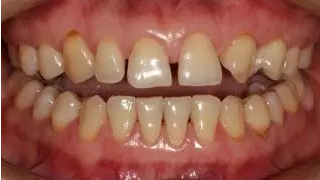

病例分享|復(fù)合樹脂微創(chuàng)美學(xué)修復(fù)關(guān)閉上前牙間隙

術(shù)前全牙弓咬合照